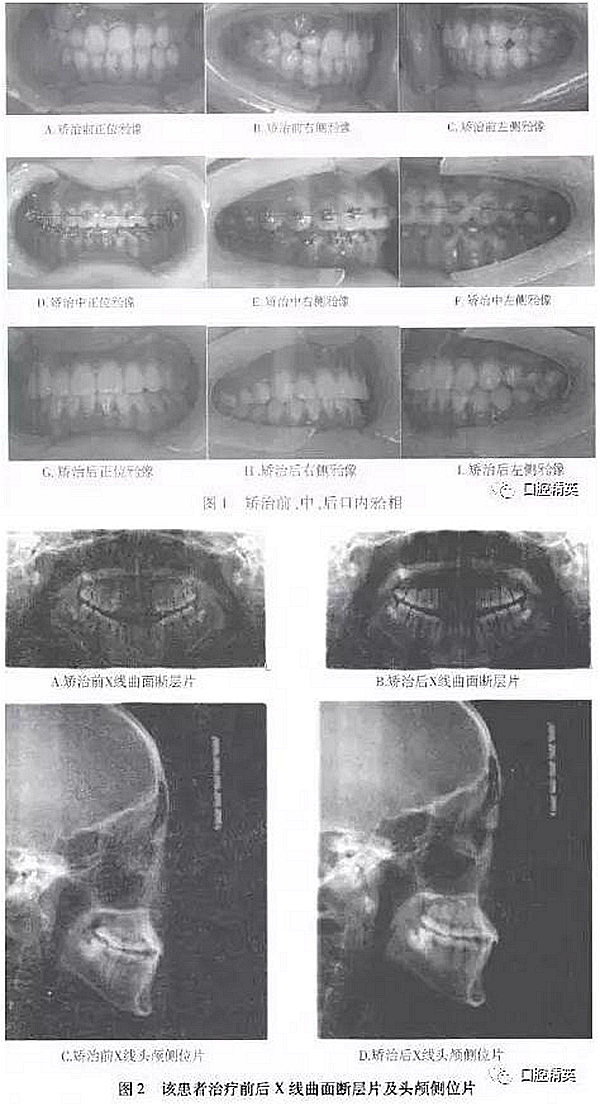

矯治結(jié)束后,患者上下牙合牙列整齊,前牙覆牙合、覆蓋正常,上下中線居中一致,雙側(cè)磨牙、尖牙均達(dá)中性關(guān)系。X線全景片顯示牙根發(fā)育及傾斜度正常,頭顱側(cè)位片顯示上頜齒槽骨得到進(jìn)一步發(fā)育,上頜骨突度達(dá)到正常值(見表1,圖1,2)。軟組織正面外貌改善顯著,面部左右對(duì)稱無(wú)偏斜。

④X線檢查:全口曲面斷層片顯示,上下牙臺(tái)四個(gè)象限均有智齒低位埋伏阻生;頭顱定位側(cè)位片測(cè)量分析結(jié)果見表1。